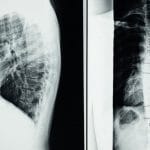

Qu’est-ce que la Décompression Spinale ?

La décompression spinale consiste en une série de traitements qui utilisent des méthodes mécanisées pour mobiliser les articulations et réduire la pression sur les disques intervertébraux. Les dispositifs comme la table de décompression neurovertébrale, tels que le SpineMED®, sont conçus pour éprouver des forces décompressives automatiques. Cette technologie permet d’atténuer les tensions musculaires et d’améliorer la circulation sanguine, favorisant ainsi la récupération des tissus endommagés.

La technologie de la décompression neurovertébrale, comme utilisée dans les cliniques TAGMED, s’appuie sur des appareils sophistiqués conçus pour mobiliser les articulations tout en diminuant la pression sur les disques intervertébraux. Ces appareils, comme la table de décompression SpineMED®, permettent une approche personnalisée du traitement. Ils intègrent des capteurs de résistance qui analysent les réactions musculaires du patient, garantissant ainsi un soin adapté et sécuritaire.

Les dispositifs tels que la table de décompression neurovertébrale SpineMED illustrent clairement l’évolution de cette thérapie. Grâce à des mécanismes sophistiqués, ces équipements permettent de mobiliser les articulations tout en désamorçant les tensions musculaires réflexes, garantissant ainsi un traitement en toute sécurité et sans effets secondaires. Cette approche ciblée témoigne de la volonté de personnaliser les soins, en s’adaptant aux besoins spécifiques de chaque patient.